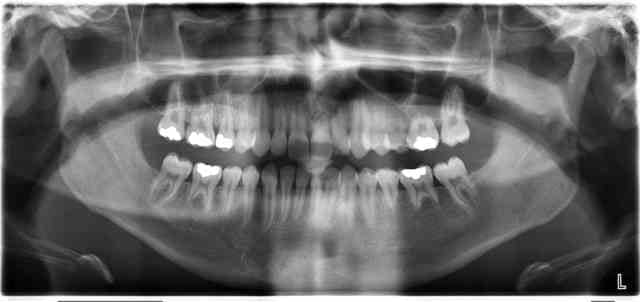

avec atteinte des 15/16/25/26/35/36/45/46

quelques facettes d'abrasion certes

mais pourquoi sur les 6 et les 5?

hygiène , hygiène et prier pour qu'il n'y ait pas d'endo car certains apex sont bien ouverts

Interposition latérale de la langue?